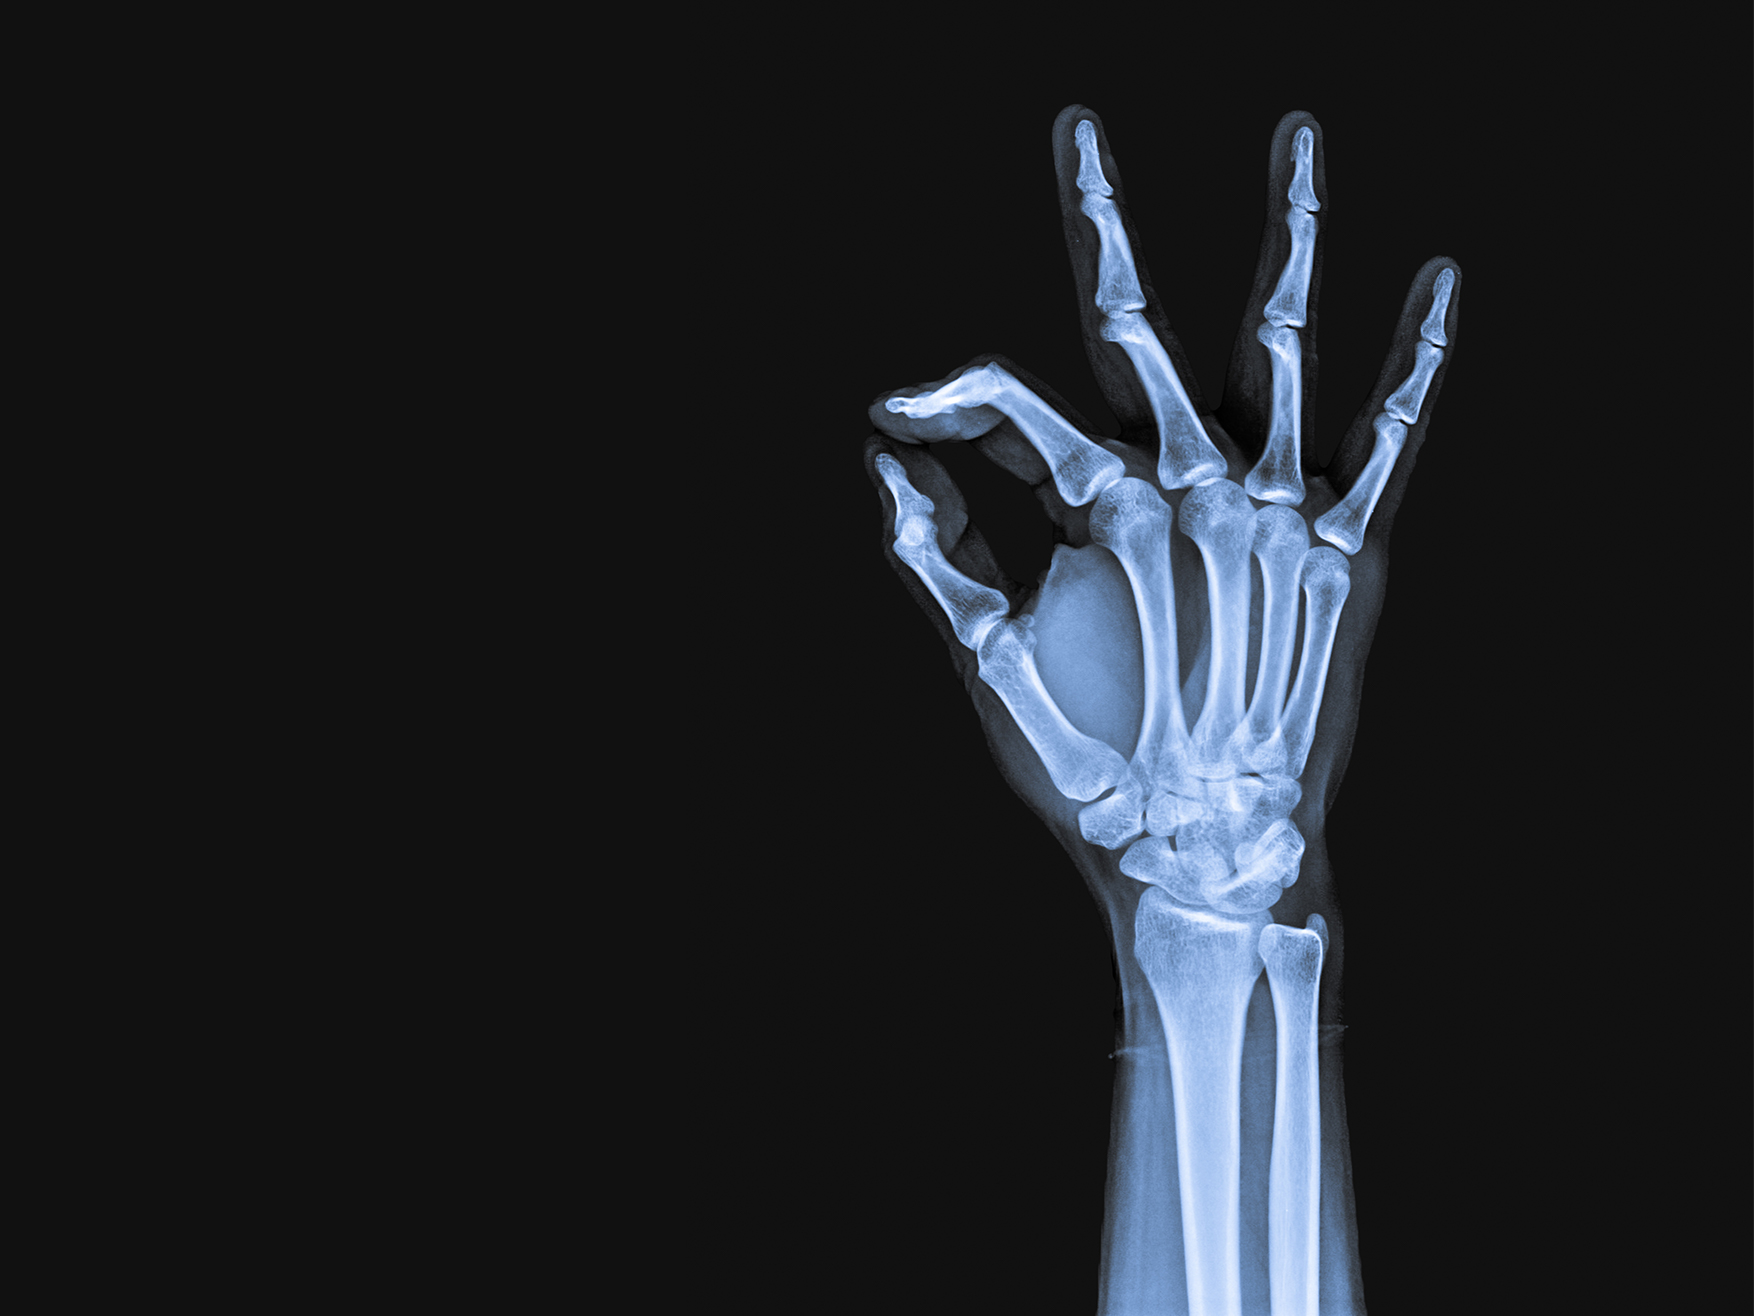

Hai mai visto uno scheletro grasso? Come è possibile allora che alcune persone sembrino avere ossa pesanti? Beh, non è così. Non puoi avere ossa pesanti. Ciò che può accadere è avere un eccesso di grasso.

Quindi, l'idea che non riesci a perdere peso perché hai ossa pesanti è una sciocchezza. Il peso delle tue ossa influisce solo in misura molto piccola sul tuo peso corporeo complessivo. Il tuo peso è determinato principalmente dalla massa muscolare e grassa. La differenza nella massa ossea tra persone con la stessa altezza è spesso solo di qualche centinaio di grammi.